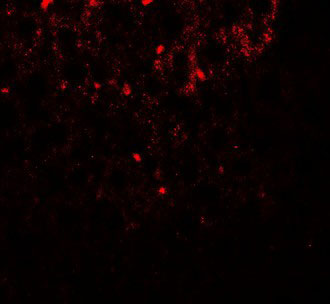

Immunofluorescence of SHBG in mouse liver tissue with SHBG antibody at 20 ug/ml. |